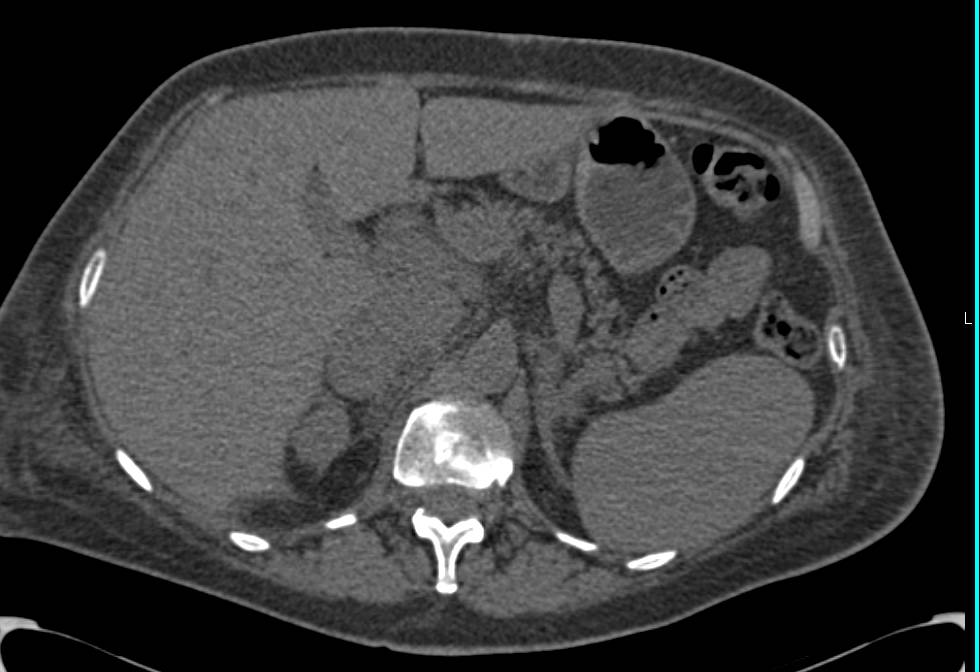

Accessory Renal Artery Upper Pole Left Kidney